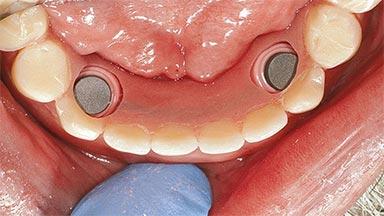

# of Implants 2

Type of Implants One-Piece

Attachment One-Piece

Defining Characteristics Fully edentulous lower jaw to be rehabilitated with an implant-borne removable overdenture